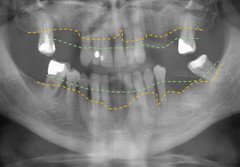

Tandlossning påverkar inte bara munnen. I en stor internationell studie kan forskare från Umeå universitet nu bekräfta att personer med tandlossningssjukdom har förhöjda nivåer i blodet av flera ämnen som är kopplade till inflammation, även om man är frisk i övrigt. En långvarig, lågintensiv inflammation kan i sin tur leda till ökad risk för andra sjukdomar.

Tandlossningssjukdom kallas också parodontit och är en av världens vanligaste folksjukdomar. I Sverige uppskattar man att ungefär 40% av den vuxna befolkningen har parodontit. Forskare vid Umeå universitet har tidigare kunnat visa att personer med parodontit har förändrade nivåer av ett tjugotal proteiner i blodet som är kopplade till inflammation, och nu bekräftas alltså resultaten i en analys av över 200 studier från hela världen som tillsammans inkluderar närmare 18 000 deltagare.